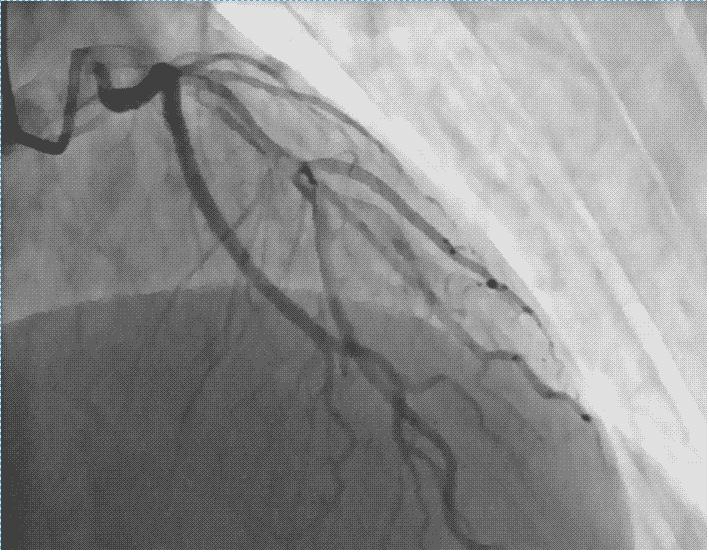

当出现胸痛、胸闷症状,同时合并有高血压,高血脂,等心血管危险因素时,那么就需要高度考虑冠心病。冠心病的检查分为两大类,一类是无创检查,心电图,心脏超声,动态心电图,血糖,血脂等检查,通过这些检查,结合患者的症状,由心血管内科的专科医生进行评估可以初步进行冠心病诊断。另一种就是冠状动脉造影,目前是诊断冠心病的金标准,通过桡动脉或股动脉将一根微导管送至心脏冠状动脉进行造影,明确冠状动脉有无狭窄或堵塞,如果造影明确冠状动脉堵塞,我们可以同时进行冠状动脉支架植入术。所以针对那种症状特别典型的患者,我们推荐冠状动脉造影检查,因为冠状动脉造影既是一个检查,同时如果冠状动脉病变严重又可以进行下一步针对性治疗。

冠状动脉造影

冠状动脉造影血管图形

冠状动脉支架植入过程